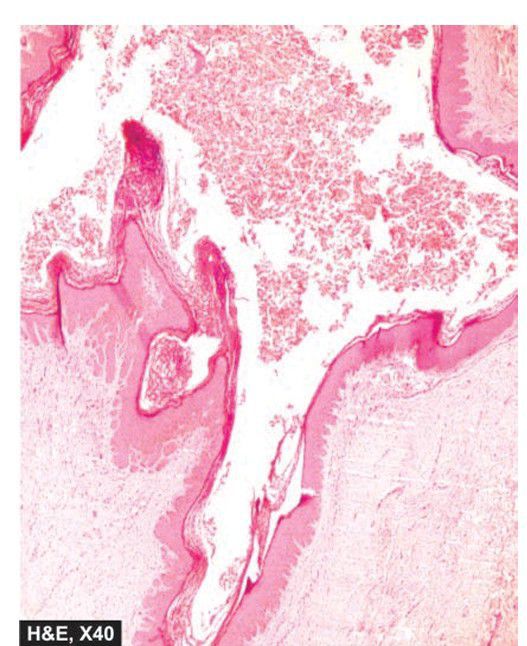

Epidermal inclusion cyst.

The cyst wall is composed of all layers of the epidermis and has laminated layers of keratin towards the lumen of the cyst.